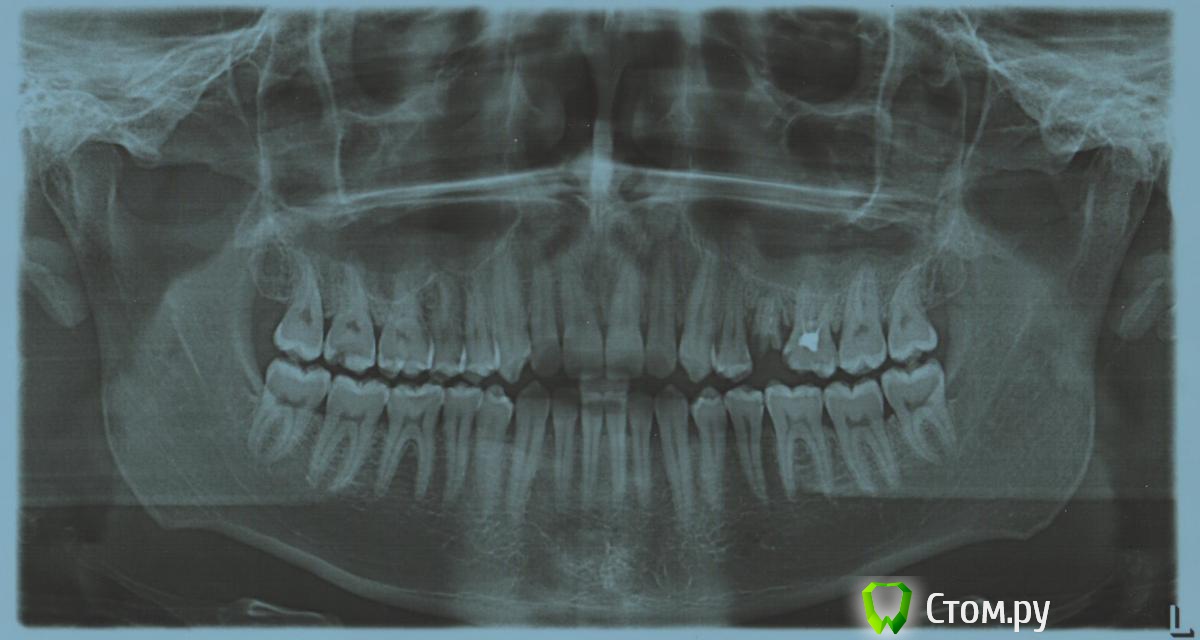

faity Опубликовано 14 августа, 2014 Поделиться Опубликовано 14 августа, 2014 А, ну это нормально. Если бы "Тридцать три" было или "Похождения зубного врача", то я бы насторожился. просто порвало))) автор выложи ОПТГ Ссылка на комментарий

Xops Опубликовано 14 августа, 2014 Автор Поделиться Опубликовано 14 августа, 2014 ОПТГ Ссылка на комментарий

faity Опубликовано 14 августа, 2014 Поделиться Опубликовано 14 августа, 2014 2.5 удалять, 2.6 коронка, брекеты верх-низ, остальное смотреть.цены низкие, у нас например дороже, но это отдельный разговор Ссылка на комментарий

shishok Опубликовано 15 августа, 2014 Поделиться Опубликовано 15 августа, 2014 На задней поверхности 24 тоже похоже кариес.Проверьте. Ссылка на комментарий